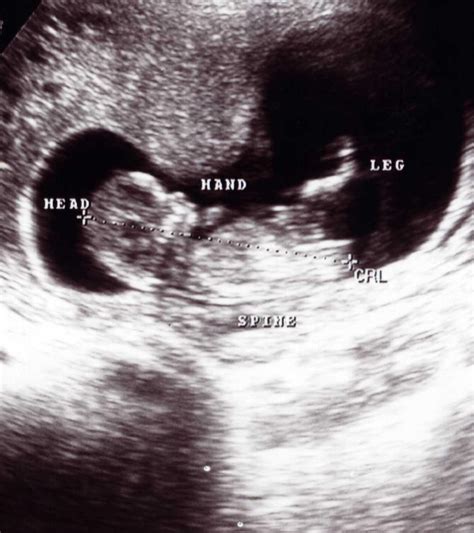

The Crown Rump Length is defined as the measurement of a fetus from the top of its head (the crown) to the bottom of its buttocks (the rump). Because fetuses typically spend the first trimester curled in a fetal position, it is impossible to measure them from head to toe. Therefore, this measurement excludes the length of the legs, which are tucked in, making the CRL the most accurate way to assess the size and age of an early-stage embryo or fetus.

During the scan, the sonographer identifies the top of the baby’s head and the bottom of the rump. They then use electronic calipers on the ultrasound machine to mark these two points. The software calculates the distance between them, and the computer instantly cross-references this value with gestational age databases to provide a measurement in millimeters (mm).

While the Crown Rump Length is considered the "gold standard" for pregnancy dating, its accuracy can be influenced by a few variables. Sonographer experience is paramount; if the calipers are placed incorrectly by even a millimeter, it can change the estimated gestational age by several days. Additionally, the position of the fetus matters—if the baby is hunched over or extended, the measurement might be slightly off. This is why a high-quality ultrasound image is essential for a precise reading.